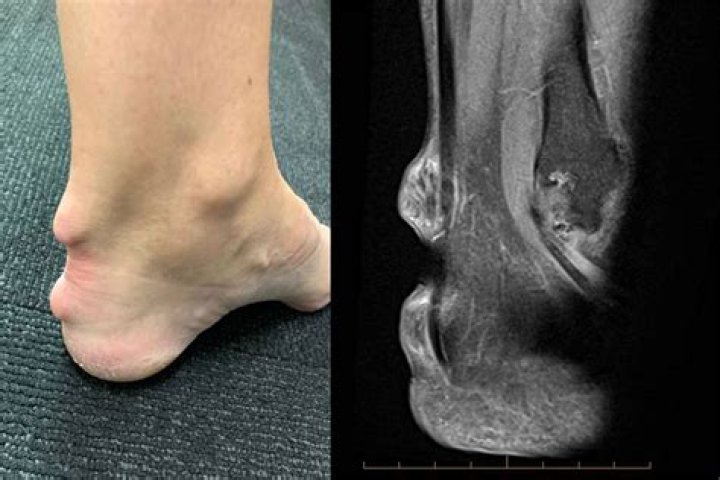

Plant thorn synovitis, also known as plant thorn arthritis, is a rare and commonly overlooked cause of arthritic disease. This disease is attributed to a granulomatous inflammatory response to retained plant thorn fragments following a puncturing plant thorn injury.

How do you know if you have plant thorn arthritis?

The diagnosis of plant thorn arthritis is made by detection of a piece of thorn within the joint by imaging tests or surgical removal and identification of the thorn fragments. The involved joint may be swollen, painful, reddened, stiff, and may have a reduced range of motion.